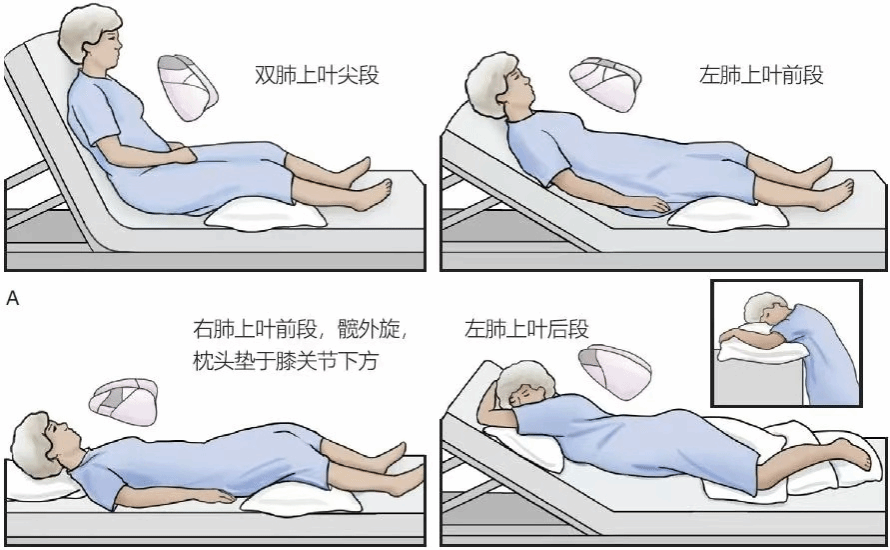

4.清除气道分泌物:包括物理排痰和化痰药物。物理排痰如体位引流、振动排痰、雾化吸入、正压通气、主动呼吸训练等。药物包括黏液溶解药、痰液促排药、抗氧化药等。

3.对大量脓痰病人,学会体位引流的方法。

6.体位引流方法: